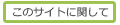

距 骨 (きょこつ、英:talus)

| か行 | ・ 外果面 ・ 外側結節 ・ 距骨外側突起 ・ 距骨滑車 ・ 距骨滑車上面 ・ 距骨頚 ・ 距骨溝 ・ 距骨後突起 ・ 距骨体 ・ 距骨頭 ・ 後踵骨関節面 |

|---|---|

| さ行 | ・ 三角骨 ・ 舟状骨関節面 ・ 踵舟靭帯関節面 ・ 前踵骨関節面 |

| た行 | ・ 中踵骨関節面 ・ 長母趾屈筋腱溝 ・ 底側踵舟靱帯関節面(=踵舟靭帯関節面) |

| な行 | ・ 内果面 ・ 内側結節 ・ 二分靱帯の踵舟部関節面 |